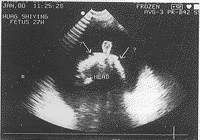

孕妇,26岁,第1胎,孕31周,常规孕期B超检查。超声显示:胎头位于耻骨联合上方,光环完整,脑中线尚居中,双顶径6.3 cm,股骨长度 5.9 cm,腹围 24.8 cm,心率150次/min。心、肝、肾、脊柱及四肢均正常,羊水深 11.0 cm。胎儿颜面部多切面扫查,于前额部见一圆管状突起,长 1.8 cm,直径 1.0 cm,用探头挤压有轻微浮动,其长轴垂直于前额,与胎儿上唇之间未见外鼻回声,仅示一不规则的凹陷(图1)。于颜面部反复横切扫查,未测及眼球回声及眼眶结构,相当于双眼位置仅见颅骨骨骼强回声(图2)。超声诊断:①胎儿管状鼻(异位于前额处)畸形?②胎儿无眼球畸形;③羊水过多。孕妇入院,分娩一女婴,娩出时尚能用口呼吸,呈“鱼吐泡样”,不久死亡。尸体检查:面部无正常外鼻突起,相当于鼻位置按压,为硬性骨质结构,于眉弓之间见一象鼻样的细管状软组织结构,大小与超声测量相同,其端部中心有一直径 0.3 cm的小孔,探针探查为一盲管。且未见正常双眼眶结构,相当于正常鼻根处触及一不规则菱形骨质缺损区,呈裂隙样,酷似双侧异常眼眶的畸形融合,表面有一层薄膜状软组织覆盖,无眼球。最后诊断:①异位管状鼻畸形;②无眼球畸形;③眼眶发育畸形;④羊水过多。

图1 颜面部正中纵切面,箭头示口唇,双箭头示外鼻缺如,三箭头示异位管形鼻

图2 眼眶水平横切面,箭头示无眼球回声, http://www.100md.com